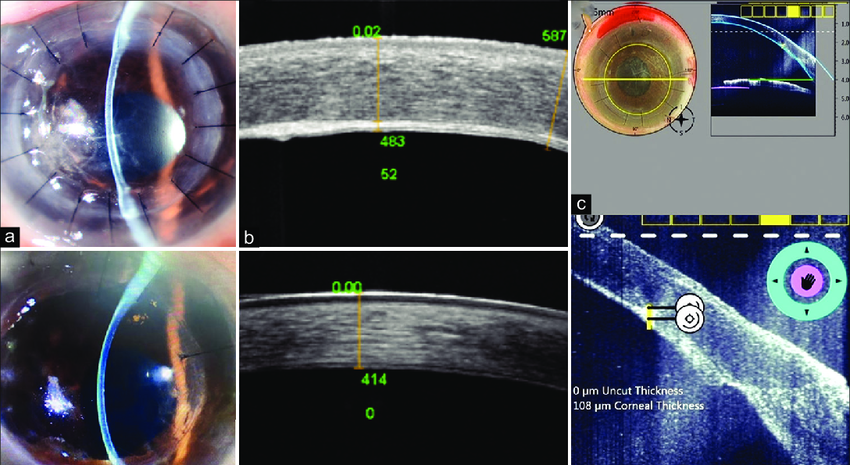

흔히 라식, 라섹을 하면 안되는 이유가 되는 병으로서,

2002년, 아벨리노각막이상증 환자에서 라식후 각막혼탁이 증가되는 최초의 증례를 발표한 이래

아벨리노각막이상증에서 라식 수술은 금기시되어 왔습니다.

라식 수술시 각막편을 만들고 레이저로 조직을 절제하는 것이

TGF-β를 포함하는 cytokine의 형성을 증가시켜서

결과적으로 각막편 사이에 서서히 hyaline의축적을 유도하기 때문입니다.

라식 수술을 하는 경우와 라식 절편을 들고 수술칼날을 이용한 기계적 각막혼탁제거를 시행한 경우 모두

수술 초기에는 각막 혼탁이 호전이 되었다가 각막 외상이 가해진 불규칙한 수술 경계면을 따라

침착물이 생기면서 더 심하게 나빠지게 됩니다.

반면에 심층층판각막이식술(Deep Ant. Lamellar Keratoplasty, DALK)은 각막세포에 적은 기계적인 외상을 가하고

각막 혼탁의 원인이 되는 각막침착물을 만들어내는 keratocyte를 완전히 제거하는 치료이기에 오랜기간 재발없이 유지됩니다.